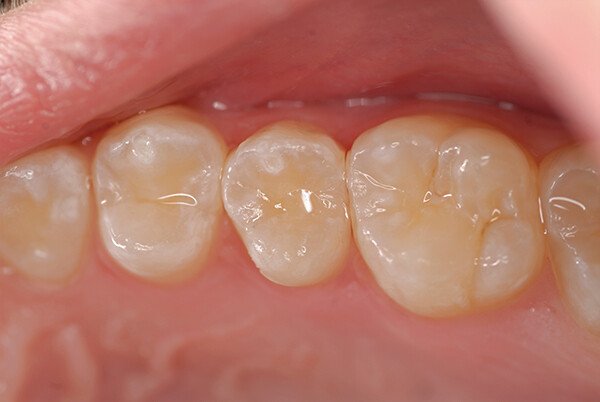

Была проведена консервативная подготовка (Рисунок 5). Капсула EQUIA Forte HT Fil перемешивалась в течение 10 секунд, материал шприцем вводился в препаровку в течение 10 секунд, конденсировался и контурировался. Через 2 минуты и 30 секунд после смешивания был нанесен и светоотвержден EQUIA Forte Coat (рис. 6); как видно, материал хорошо сочетался с цветом зуба.